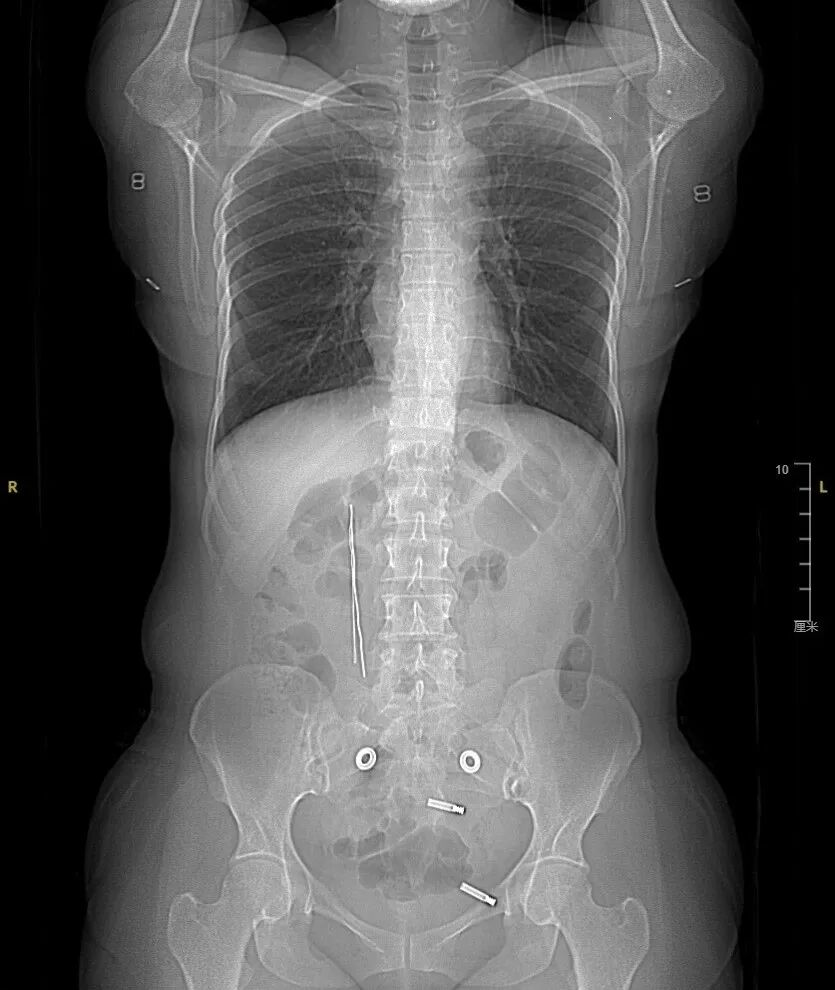

CT检查提示,患者十二指肠球部至降部内可见高密度金属影、伴放射状伪影,考虑异物嵌顿于十二指肠。消化内科副主任、病区主任曹彬,副主任医师刘俊衡仔细分析检查影像、询问患者病情,认为异物若不及时取出,一旦穿孔,患者将会有出血、感染等并发症发生。由于患者腹内钢丝嵌顿时间较长,且在十二指肠的嵌顿深度不明确,内镜取出存在较大风险,也面临着实施开腹手术干预的可能。

术中发现钢丝形态质地正常,钢丝尖端均用塑料外皮包裹,一端嵌顿于十二指肠球部前壁,一端嵌顿于十二指肠降部。刘俊衡副主任医师操作胃镜精准地利用异物钳松动钢丝嵌顿部,通过异物钳结合圈套器成功将两根约10厘米长的钢丝取出。患者术后顺利返回病房,未再有腹痛、腹胀等症状发生。